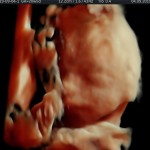

Modalidad de imagen ecográfica que permite evaluar, medir y capturar estructuras fetales superficiales e internas en 3 dimensiones (3D) y también en movimiento y en tiempo real (4D) con programas de realismo aumentado (HD LIVE) e imágenes tomografías fetales (TUI) mejorando significativamente la precisión en las mediciones fetales y la documentaciones de estructuras anatómicas.

Esta tecnología se puede utilizar desde la 6ta a la 40ma semana de embarazo.